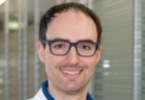

„Viele Frauen fragen, ob es eine Studie für sie gibt“

August 2021

31.08. 42/2021

31.08. 42/2021

Kombinierte Tumorimpfung verstärkt krebsabtötende Immuneffekte

„Die COVID-Impfung bringt die Krebsforschung voran“

12.06. 29/2021